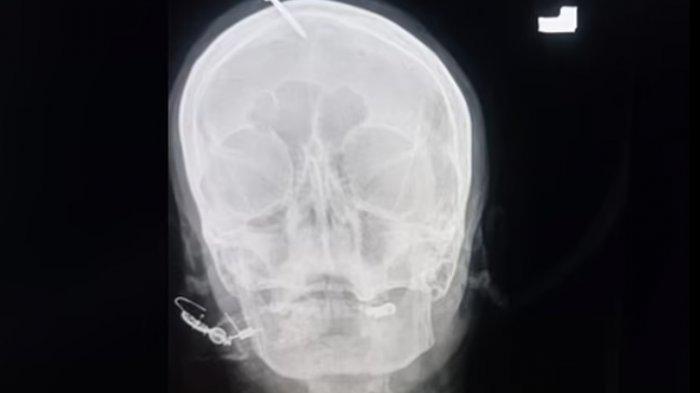

Paku ditancapkan di dahi dan menem namun tidak mengenai otak perempuan itu.

TRIBUNNEWS.COM, PAKISTAN - Seorang wanita yang tengah mengandung tiba di rumah sakit karena di kepalanya tertancap paku sepanjang 5 cm.

Atas kejadian ini, polisi mulai menyelidiki setelah gambar x-ray dari cedera beredar di dunia maya.